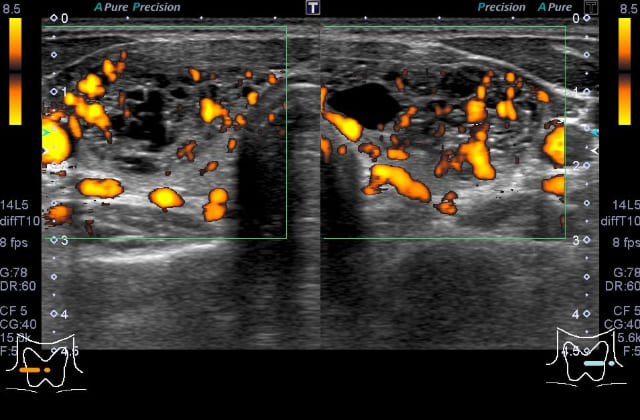

本症はバセドウ病と比べると、FT3/FT4比やFT4値が低かったり、TSH受容体抗体が陰性または低値のことが多く、甲状腺エコーで上甲状腺動脈の最高流速度も低い、などの特徴があります。本症と診断された場合は、一般的にはバセドウ病のくすりは服用せずに経過観察をします。甲状腺ホルモンが過剰の時期から低下症の時期を経ますが、多くは2ヶ月程度で正常に戻ります。低下症になってすぐには、低下症が継続するかの判断は難しく(抗甲状腺関連抗体陽性例では低下症継続の率が上がることは参考になります)、この時期で開始した補充療法は途中で中止できる可能性があります。

機能性結節は孤発性(プランマー病)、多結節性に分かれます。どちらも持続性の甲状腺ホルモン過剰(甲状腺ホルモン亢進症)の原因となります。甲状腺機能ホルモンの上昇は軽度のことが多く、潜在性甲状腺機能亢進症の原因としても知られています。TSH受容体抗体が陰性で、甲状腺エコーにて(のう胞を伴うことが多い)血流豊富で大きな腫瘤を認めた場合に本症を疑います。この場合は、核医学検査(甲状腺シンチグラフィー;放射性ヨウ素やテクネシウム)で結節に一致した取り込みと結節外での取り込み抑制を確認して診断となります。機能性腫瘍は基本的に良性ですが、本症が疑われた場合は、核医学検査が行える医療機関へご紹介いたします。孤発性の場合は一般的に外科治療が選択されます。

甲状腺超音波(エコー)検査では、甲状腺は基本的には全体的に大きくなり、内部は粗くみえることが多いです。臨床診断は、甲状腺の全体的な腫大に加えて、TgAbまたはTPOAb陽性で行います。甲状腺機能が正常であれば治療の必要はありません。機能が低下している場合には飲み薬(チラーヂンS®、レボチロキシン®)によって甲状腺ホルモンの補充を行います。服用は一日一回です。(吸収の安定性からは空腹時の服用がよく、また金属系製剤と同時服用は避ける必要があります)